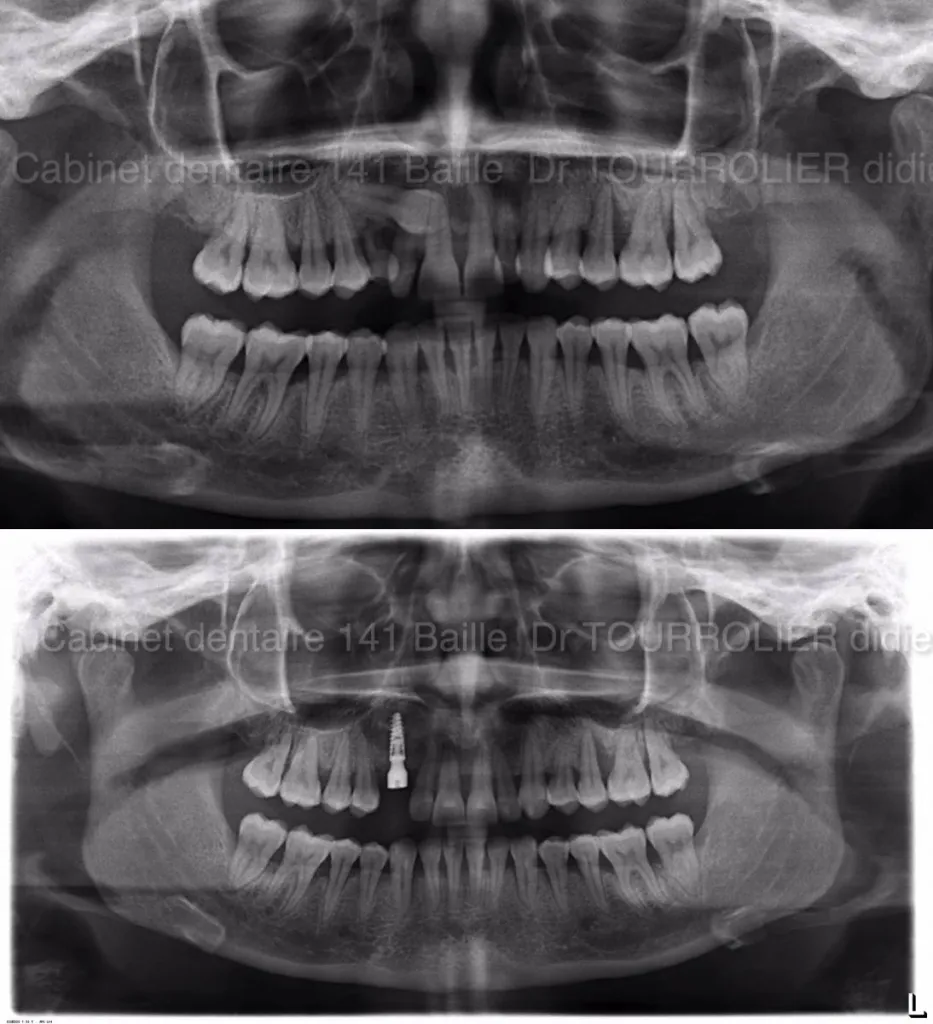

Traitement d'une canine incluse par Implantologie.Dr TOURROLIER Didier

Discussion au sujet du remplacement d'une canine incluse mal placée par une technique implantaire combinée à une greffe osseuse.